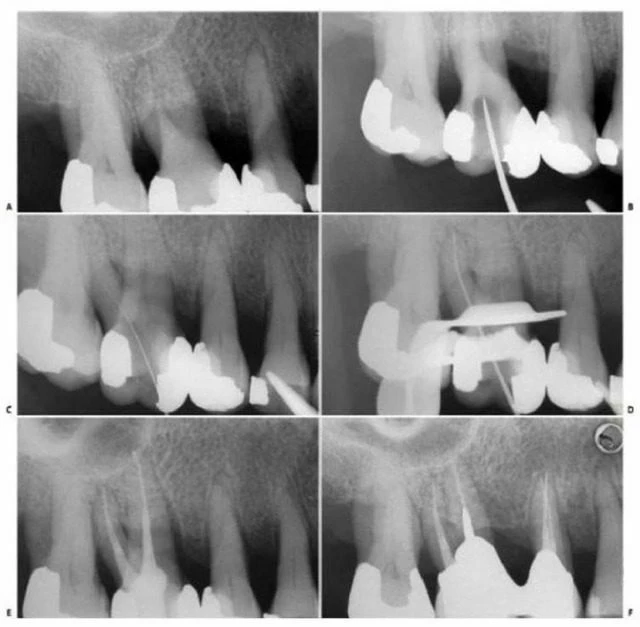

Ở những ống tủy cong, vị trí thành xoang đối diện với đoạn cong chân răng phải được mở rộng (hình 11.14). Nhằm đảm bảo dụng cụ không bị cong hơn so với độ cong vốn có của chân răng. Tương tự như lúc xe chạy vào khúc cua vậy, người ta thường tăng bán kính khúc cua để xe không bị chạy ra khỏi làn đường.

Hình 11.14. A. Phim trước điều trị R36: chân gần cong 1/3 trên. B. Mở đầu bằng trâm số #8 đi vào ống ngoài gần, nhận thấy ống tủy cong về phía xa và phía lưỡi. C. Xoang tủy được mở rộng về phía gần và phía má, phạm vào múi gần ngoài. D. Trâm số #20 có một đường vào thẳng đến 1/3 chóp của ống tủy.